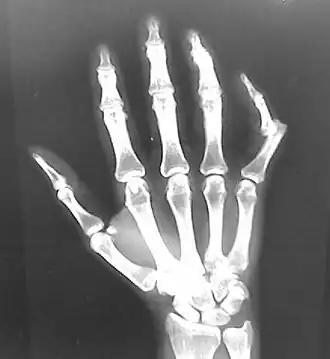

- Interphalangeal (IP) or metacarpophalangeal (MCP) joint dislocations[41]

- In the United States, men are most likely to sustain a finger dislocation with an incidence rate of 17.8 per 100,000 person-years.[42] Women have an incidence rate of 4.65 per 100,000 person-years.[42] The average age group that sustain a finger dislocation are between 15 and 19 years old.[42]

- The most common dislocations are in the proximal interphalangeal (PIP) joints.[8]